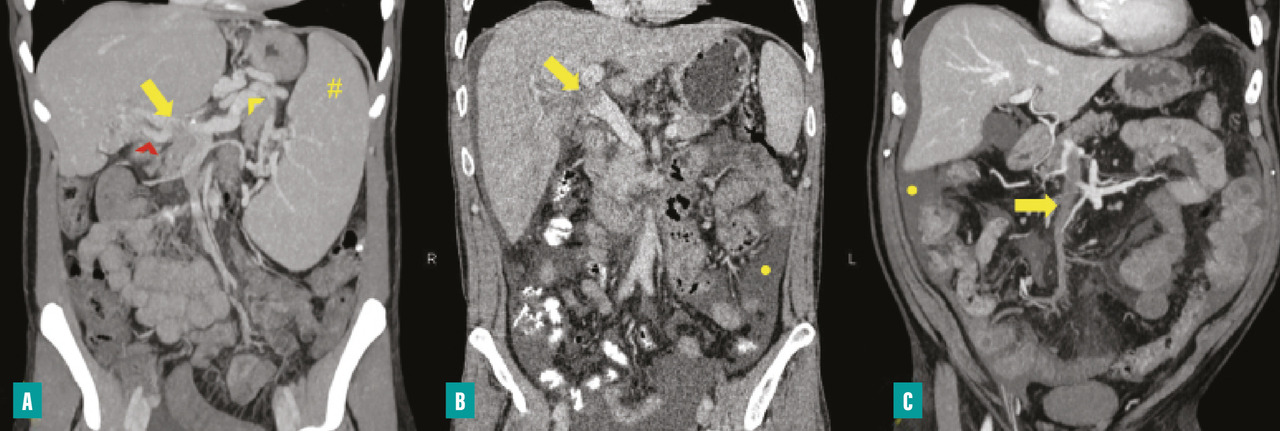

Pour la TVP chronique sans hépatopathie chronique sous-jacente, la recanalisation de la veine porte par voie radiologique doit être envisagée en cas de complications réfractaires au traitement médical, comme des hémorragies digestives liées à l’hypertension portale non contrôlées par un traitement endoscopique, ou en cas de cholangiopathie portale symptomatique (fig. 4). La recanalisation portale s’effectue par la pose d’un stent dans la veine porte  ; elle peut être associée à la pose d’un TIPS (transjugular intrahepatic portosystemic shunt) L’abord peut être transhépatique, transsplénique ou transmésentérique. Cette procédure de radiologie interventionnelle est complexe et nécessite une prise en charge multidisciplinaire dans un centre expert, ce qui permet d’obtenir un succès technique de 80  % environ, mais au prix d’un taux de complications d’environ 20  %.21,22

Le diagnostic de TVP récente repose sur l’imagerie. Elle doit être réalisée chez tout patient qui en présente une suspicion clinique. L’échographie-Doppler est généralement l’examen de première intention  ; elle permet la visualisation directe du thrombus dans la veine porte et l’absence de flux au Doppler en cas de TVP complète (sensibilité de 88 à 98  %, spécificité de 80 à 100  %). Elle doit être complétée systématiquement par un scanner (ou une imagerie par résonance magnétique [IRM]) abdominal avec injection de produit de contraste, et aux quatre temps d’acquisition (sans injection, phase artérielle, portale et tardive), si cette imagerie n’a pas été réalisée d’emblée. Le scanner permet de confirmer le diagnostic de TVP, de déterminer le degré d’extension aux veines spléniques et mésentériques, de rechercher un facteur local et des signes d’ischémie mésentérique. De plus, il permet d’identifier des signes d’hépatopathie chronique sous-jacente (dysmorphie hépatique, signes d’hypertension portale) [fig. 2].

Le diagnostic de TVP chronique repose également sur le scanner (ou l’IRM) avec injection de produit de contraste, mettant en évidence l’absence de visualisation de la veine porte, généralement remplacée par un cavernome.